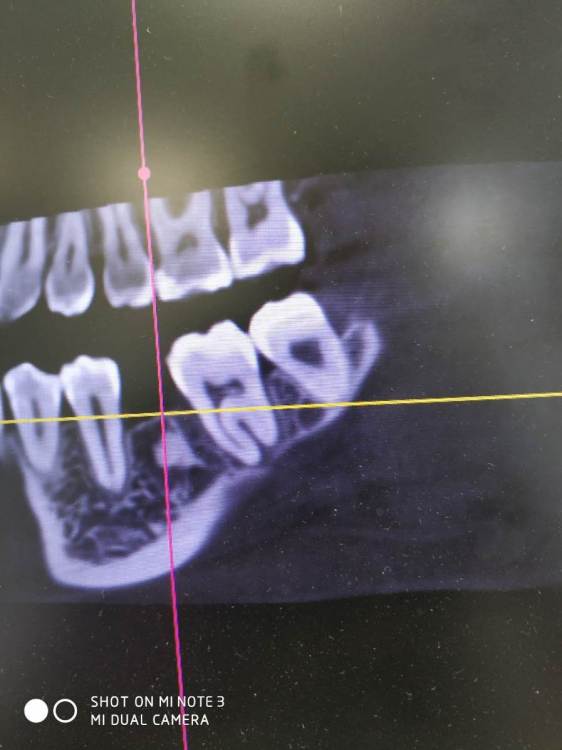

Raystom Опубликовано 16 мая, 2021 Поделиться Опубликовано 16 мая, 2021 (изменено) На общей ниве задам вопрос. Как правильно поступить, засверлиться медиальнее или засверлиться, ушить, подождать 3 недели и установить имплантат. Со слов в этом месте 1.5 года назад удаляли резорциненный 36. По КТ не видно рельефа кости в общем и есть эностоз в середине. Ортодонтически пытались двигать 37, 38 вперёд - не выходит. Изменено 16 мая, 2021 пользователем Raystom Ссылка на комментарий

It'sGeorgy Опубликовано 16 мая, 2021 Автор Поделиться Опубликовано 16 мая, 2021 Вы вот так ставить планируете? Если да, то, имхо, немного смысла в предварительном препарировании. Вы весь этот остеоид высверлите практически. Ссылка на комментарий

Raystom Опубликовано 16 мая, 2021 Поделиться Опубликовано 16 мая, 2021 В том-то и дело, что не весь, а дистальная стенка имплантата будет в контакте с образованием Ссылка на комментарий

Женька Опубликовано 16 мая, 2021 Поделиться Опубликовано 16 мая, 2021 Это же кость, разве нет? почему бы не относится к ней как к кортикальному слою? Ссылка на комментарий

Raystom Опубликовано 16 мая, 2021 Поделиться Опубликовано 16 мая, 2021 2 часа назад, Женька сказал: Это же кость, разве нет? почему бы не относится к ней как к кортикальному слою? В принципе так и думал, но смущает пару моментов, получу ли я не только механическую стабильность, а ещё и последующую интеграцию при одномоментном подходе и смущает островок плотной кости на фоне крупноячеистой кости. В остальных участках кость выглядит как D2 на всем протяжении Ссылка на комментарий

АнтонТЛТ Опубликовано 16 мая, 2021 Поделиться Опубликовано 16 мая, 2021 Кровь все равно будет в этой области, поэтому интеграция будет) Если ссыкатно, то первым этапом препарирование ложа, через 1,5-2 месяца установка имплантата в свежую кость. 1 1 1 Ссылка на комментарий